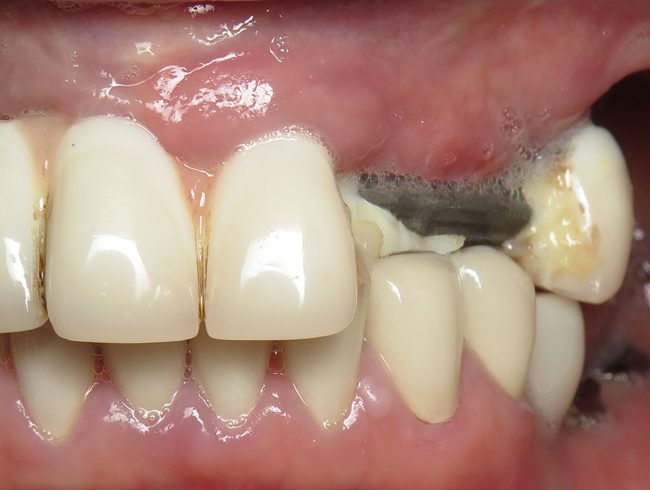

Secondary Dental Caries

Secondary (or recurrent) dental caries refers to a carious lesion associated with restorations (fillings) or sealants. The main culprit that causes decay underneath crowns is plaque and bacteria.

After the consumption of food, debris that is left on the tooth becomes a reservoir for harmful bacteria. Bacteria metabolizes the food in our teeth and converts them to acid which attacks and damages the enamel. Decay starts at the edges of natural tooth under the crown and progresses very quickly towards dentine.

Your dentist can spot decay underneath your bridge through an X-ray. If the decay is extensive, the bridge will need to be taken apart using high speed rotary instruments to access and remove all the decay. Deep carious lesions can lead to severe destruction of hard tissues and loss of even more tooth structure.